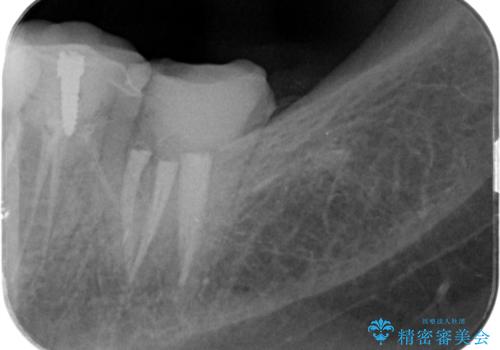

割れたクラウン 再発した虫歯の治療

- 「他院で治療したクラウンが破損したまま放置してしまった、治療したい。」、とセラミック治療を希望され来院されました。

欠けたクラウンの下には虫歯が再発し、このまま放置すると抜歯を余儀なくされる状態です。

虫歯をマイクロスコープを用いて丁寧に除去した後、ジルコニアセラミッククラウンによるクラウン製作を行います。

仕上がりの色調や自然さに満足いただくことができました。